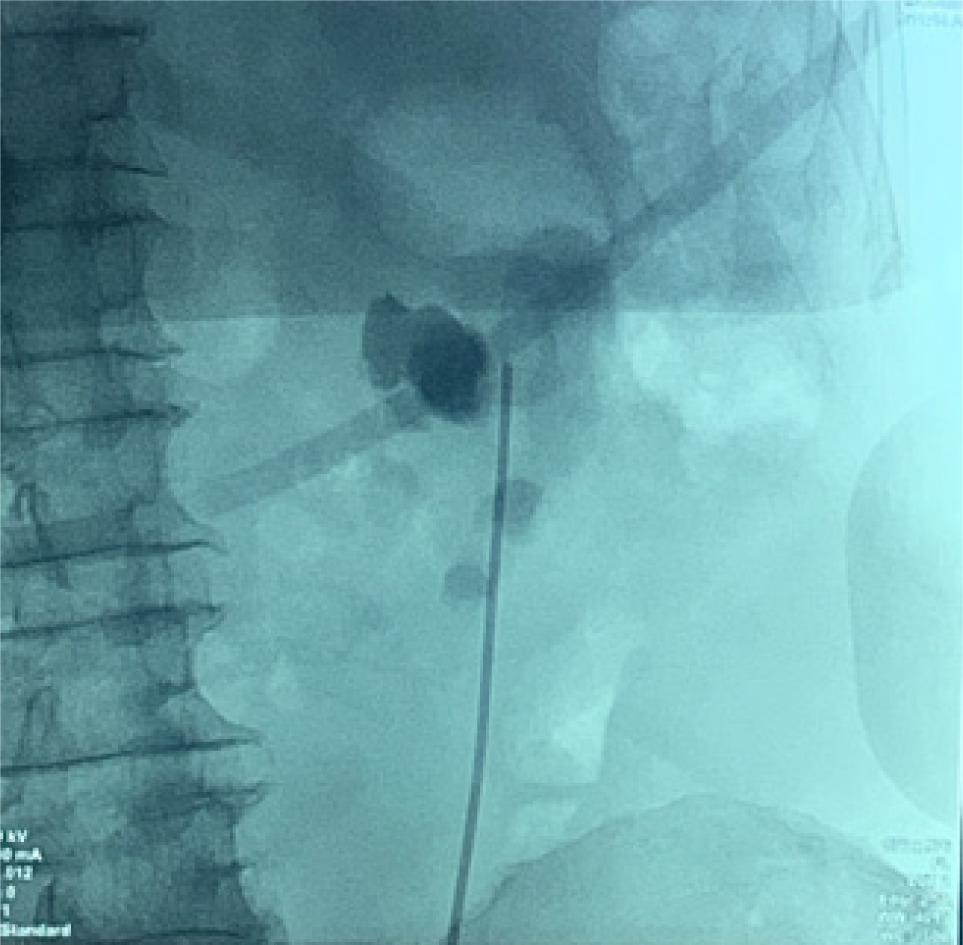

Bilateral RP and ureteric catheterization were first performed for the identification of the hila and calyces of the HSK (Figures 4 & 5). A lower midline laparotomy was performed. The tumor was identified, measuring 7 cm in diameter (Figure 6). Careful dissection of complex hilar structure was performed. Two renal arteries and two renal veins supplying the right side were identified and slung (Figure 7). The tumor was resected with artery clamping (Figure 8). The right lateral calyx of the pelvicalyceal (PC) system was involved and resected. The PC system was closed with 3/O PDS. Renorrhaphy was completed with 3/O V-Loc, and parenchyma was closed with 2/O V-Loc. Ischemic time was 20 minutes, and total operation time was 332 minutes. Blood loss was 420 mL. The patient had completed 1 week of levofloxacin and was discharged on postoperative day 6 with one kick of fever that spontaneously subsided.

Figure 4: Left renal pelvis.

Figure 5: Right renal pelvis.